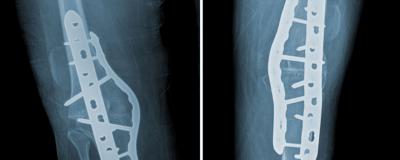

A template was employed to contour an anterior proud 4.5 x 206 mm 11-hole locking plate. The plate was inserted with two screws in the proximal segment and the articulated tensioning device was used to compress the osteotomy site. The construct was bolstered with four proximal and four distal screws. An additional 4.5 x 206 mm medial locking plate was contoured (Figure 3-A).

The patient was made non-weight bearing for eight weeks and was discharged four days postoperatively after an uncomplicated hospital stay. At three months postoperatively the patient had minimal pain and a considerably improved gait. Twelve months after the index procedure, he underwent uncomplicated instrumented arthrodesis of the left knee, with the same indication, operative technique, and methods of fixation (Figure 3-B).

Bilateral AP radiographs of the right (A) and left (B) knees demonstrating arthrodesis hardware in appropriate positions with appropriately healed surgical incisions.